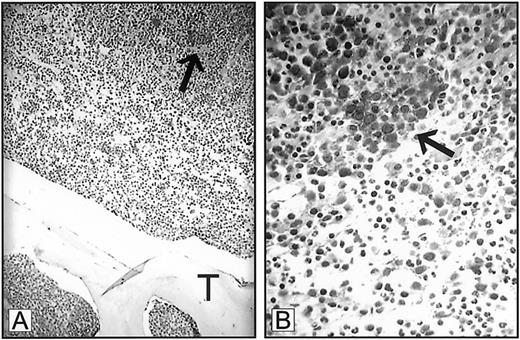

Expression of VEGF in ALIP.

Bone marrow trephine biopsy from a patient with myelodysplastic syndrome demonstrating expression of VEGF in myeloblast clusters (arrows). T indicates trabecular bone. Panel A, 250 × magnification; panel B, 1000 × magnification.

Dr Mangi interprets our data as indicating that the means by which we diagnose ALIP was based solely on findings derived from bone marrow clot sections.1-1 The definition of ALIP as originally proposed by Tricot et al1-2 1-3 resides upon resolving the spatial relationship between myeloblast clusters to bone trabeculae within trephine biopsies, as we described in “Discussion.”1(pp1432-1433) Indeed, we stress that the displacement of myeloid precursor clusters from their paratrabecular locale represents an adverse prognostic feature in MDS that is associated with an imminent risk for leukemic transformation. We do not, however, base a diagnosis of ALIP on bone marrow clot sections alone. All myeloblast clusters identified in marrow clot sections were confirmed by trephine biopsy prior to immunohistochemical staining. Our use of bone marrow clot sections to examine VEGF and receptor expression was predicated on the superior staining characteristics of bone marrow clot sections as compared to cores under the conditions used for staining in this study. Nevertheless, Mangi's letter now prompts us to include a figure showing VEGF expression in ALIP in a bone marrow trephine biopsy. Although the level of staining is not as optimal as that observed in the clot sections provided in the original manuscript, VEGF expression is clearly demonstrated (Figure1-1).